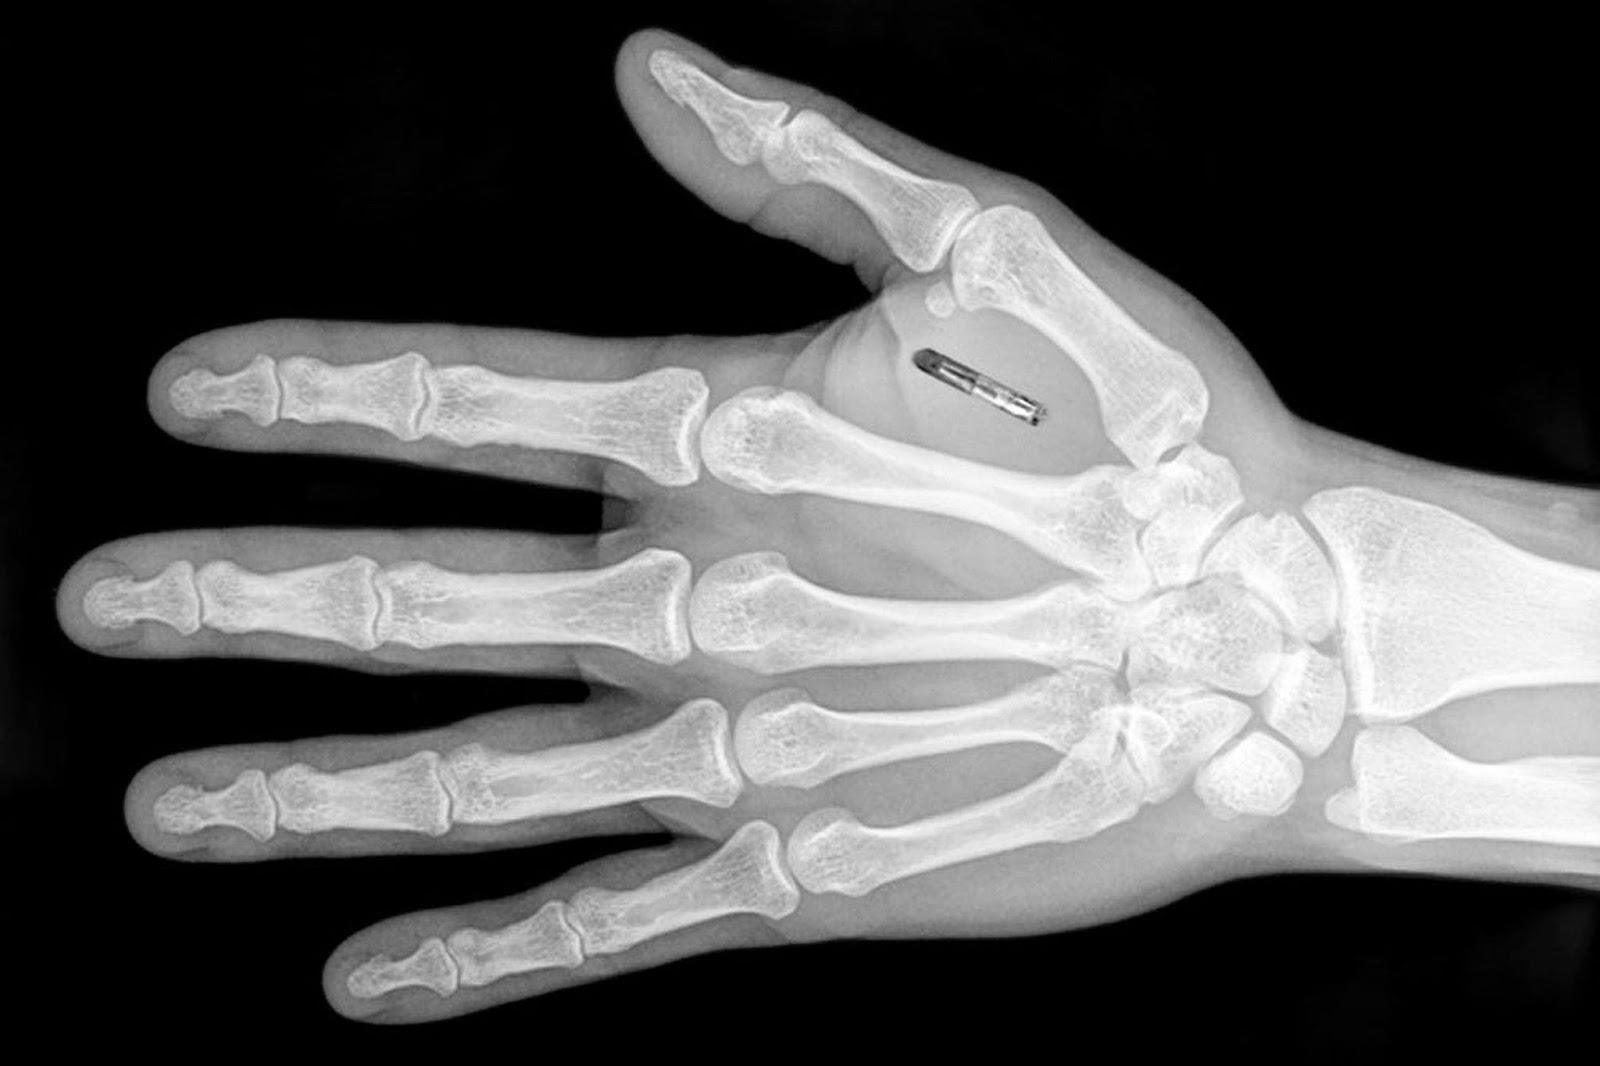

deri altina yerlestirilen cip ile her seyi yonetiyorlar yeni safak

anahtar bilet tasima derdi yok ulkede 4 bin kisi eline cip taktirdi son dakika dunya haberleri

isvecli bir firma calisanlarina cip takmaya basladi

deri alti ciplerin normallestigi isvec te bu durum artik bir trend